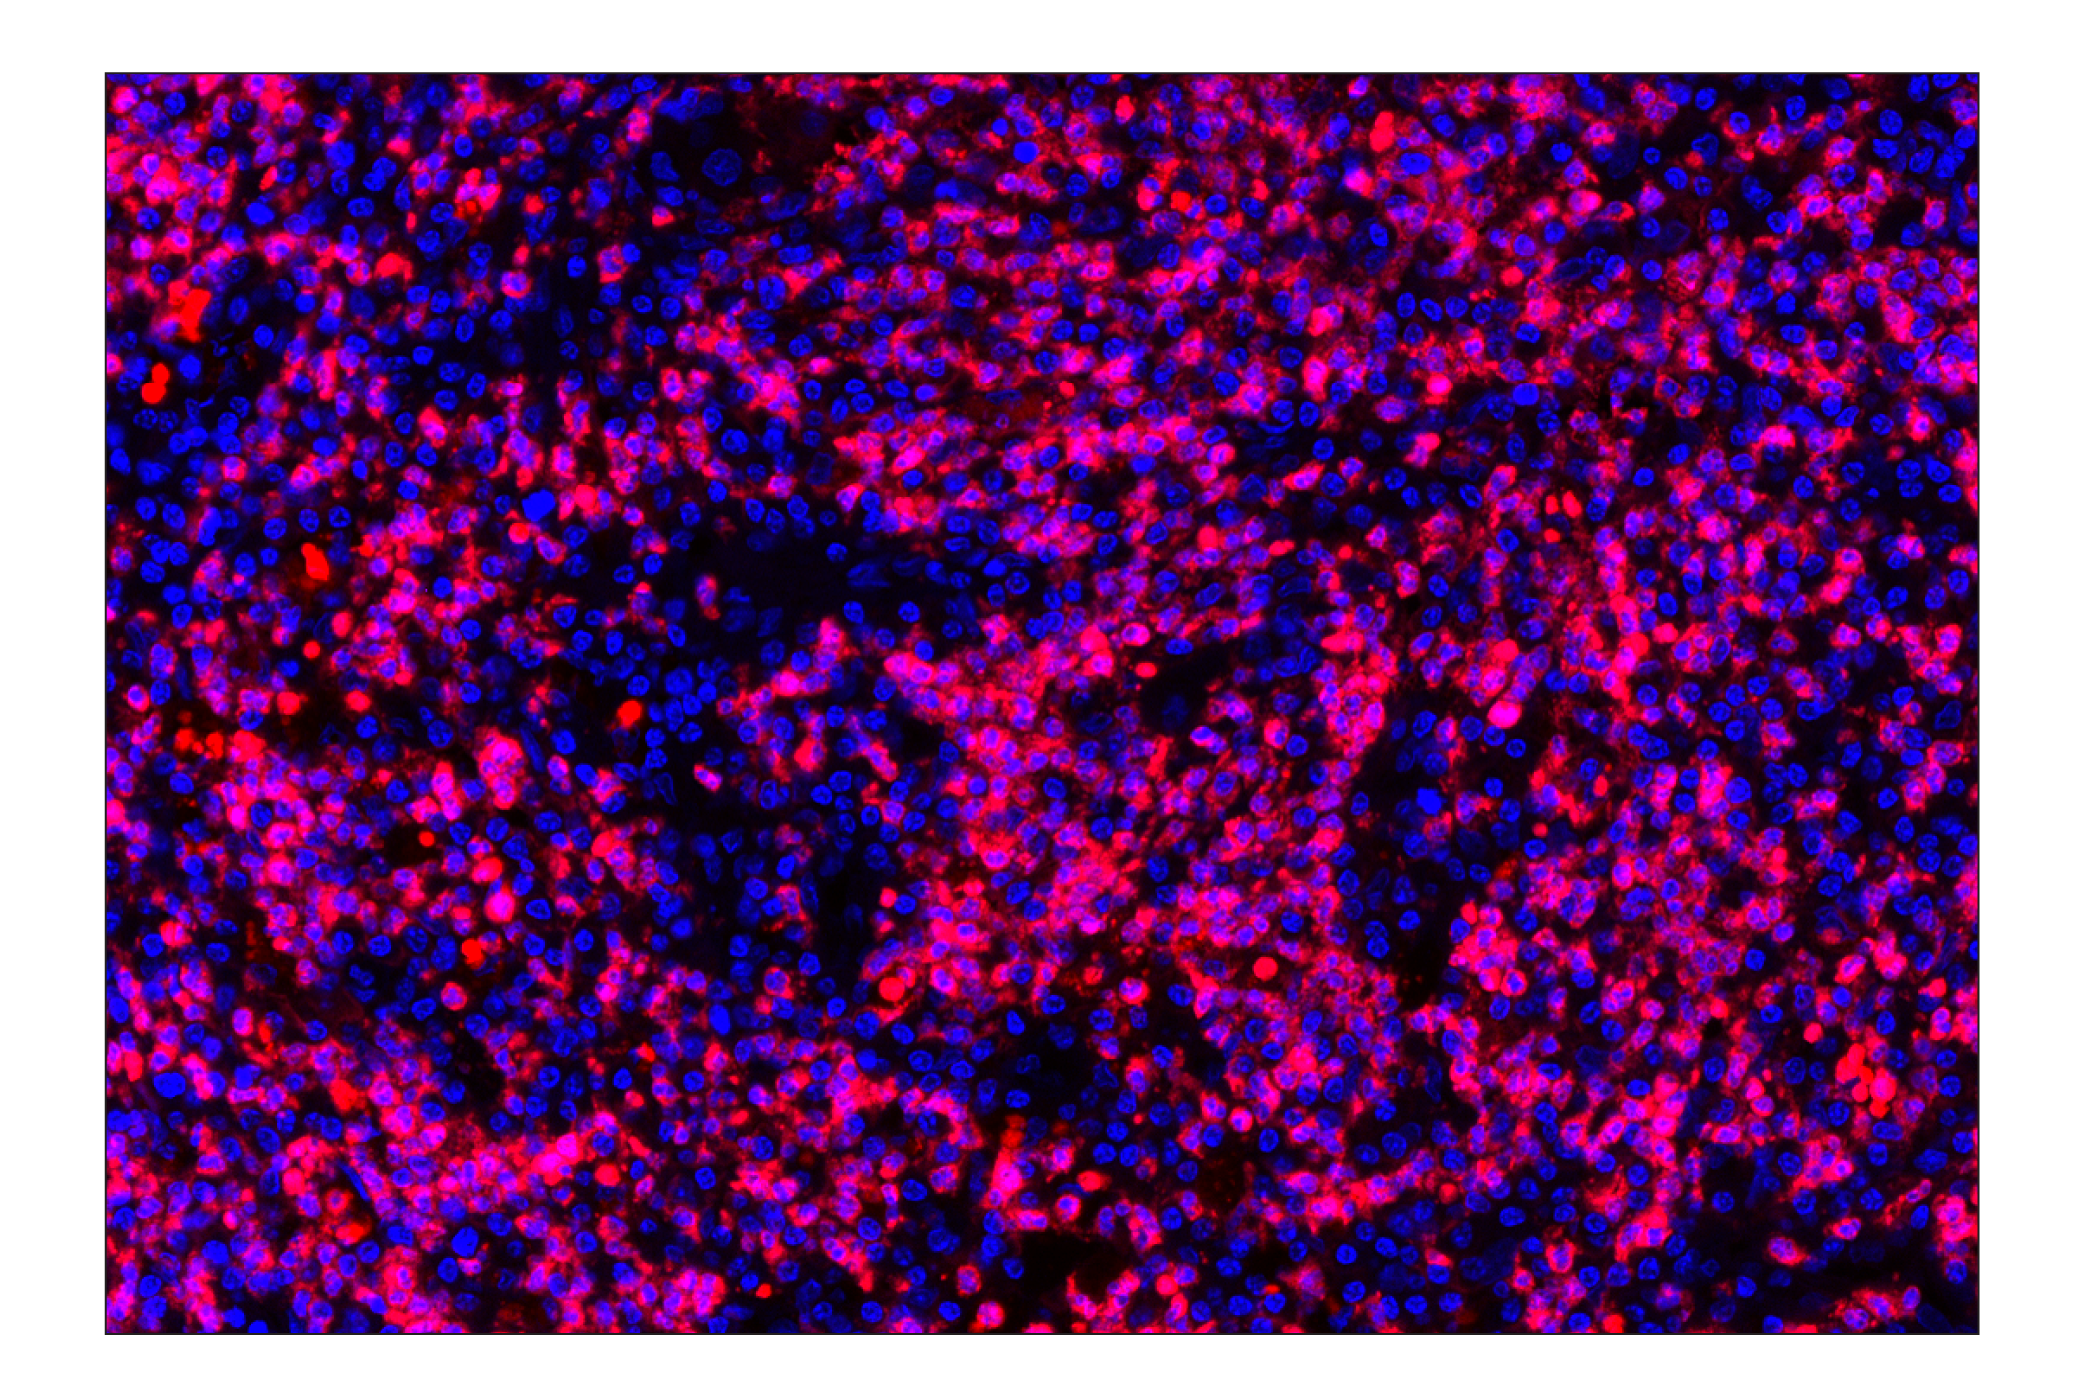

Neutrophil Elastase (F4H3X) Rabbit Monoclonal Antibody (Alexa Fluor® 647 Conjugate) #71859

Immunohistochemistry (Paraffin) 1:100 - 1:400

Neutrophil Elastase (F4H3X) Rabbit Monoclonal Antibody (Alexa Fluor® 647 Conjugate) recognizes endogenous levels of total neutrophil elastase protein. This antibody cross-reacts with pro- and mature forms of neutrophil elastase protein.